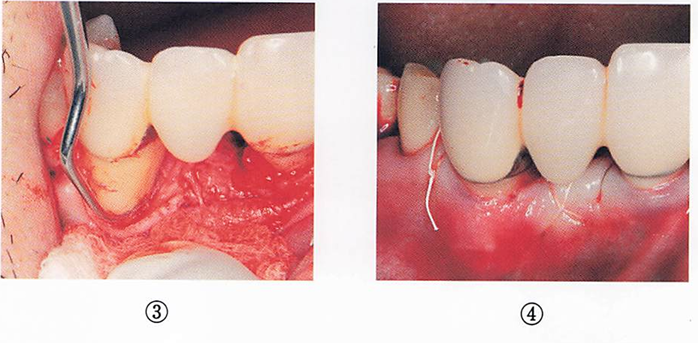

午後-44

45歳の女性。下顎左側小臼歯部の歯が伸びて見えることを主訴として来院した。歯周基本治療後に、下顎左側第一小臼歯の歯根露出に対して根面被覆を目的に歯周形成術を行うことになった。手術中の口腔内写真を別に示す。

行った手術はどれか。1つ選べ。

a.歯肉剥離掻爬術

b.遊離歯肉移植術

c.歯肉弁側方移植術

d.歯肉弁歯冠側移動術

解答を見る

b